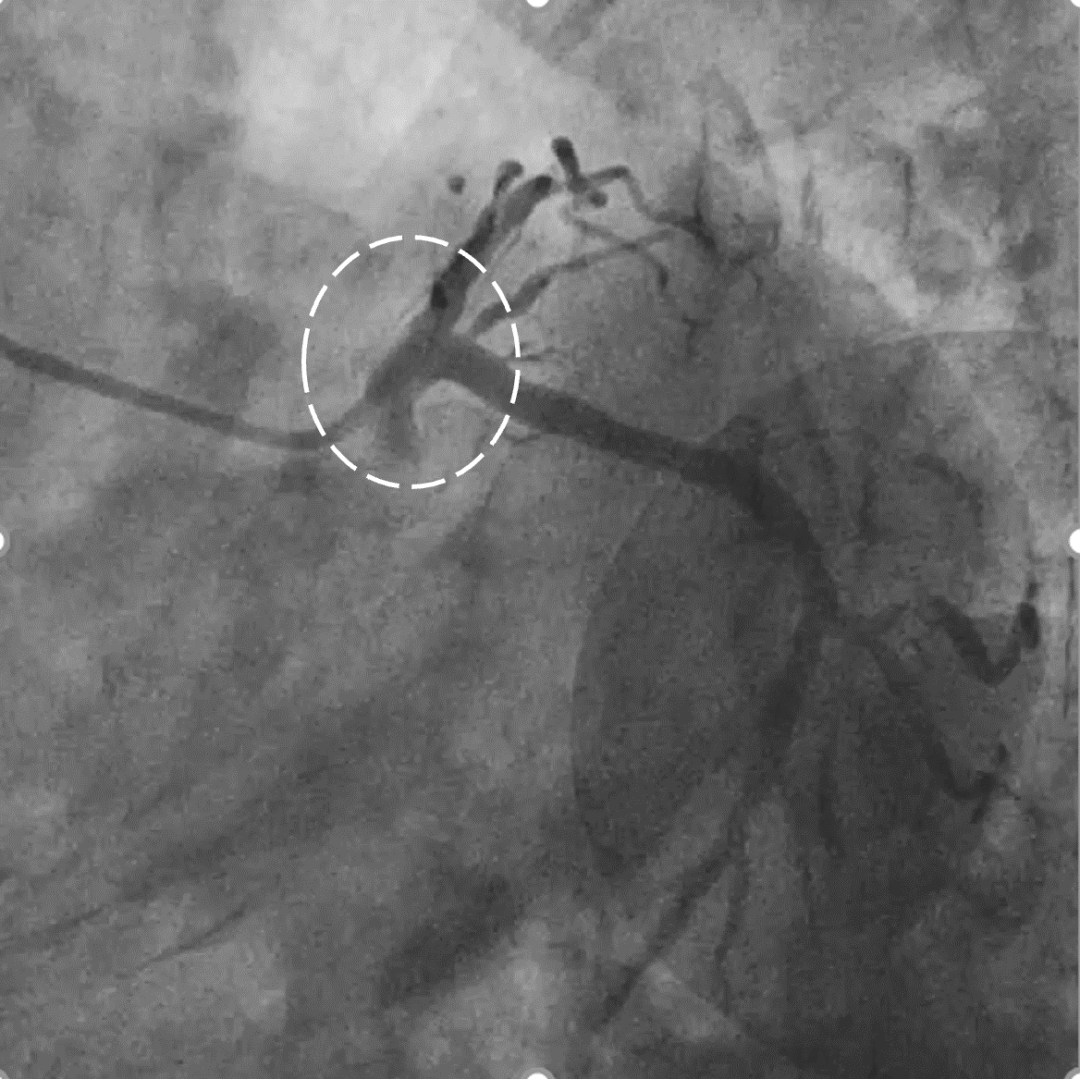

左冠优势,LM、LCX未见狭窄,TIMI3级;LAD近段CTO,TIMI0级

RCA细小,近中段狭窄40%-50%,TIMI3级;远端可见LAD侧枝血流

策略讨论:近端纤维帽不清晰,LAD中段显影可见,闭塞段长度>20mm。间隔支逆供条件尚可。CTA提示LAD多发钙化。尝试正向开通,优选亲水性滑导丝,若失败,及时调整逆向策略。

LAD、LCX双支 CTO ,LAD 近端50%狭窄

RCA粗大,支架代偿良好。远端60%狭窄,PDA开口80%狭窄

策略讨论:双支CTO,闭塞段残端清晰,钙化,右冠造影可见PLV/PDA侧供LCA。由于有前降支PCI失败史,该次已经做好充分准备,大概率需要逆向PCI。